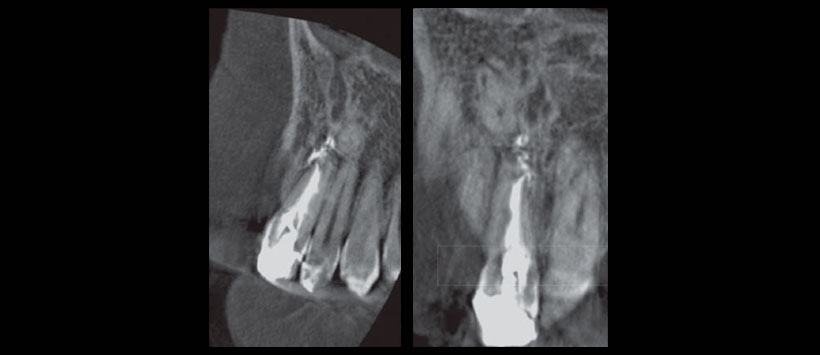

Seis meses después se repitió una tomografía cone- beam para valorar el sellado tridimensional en la zona de la perforación, observándose un buen sellado apical tanto en la perforación como en el conducto principal (Figura 3).